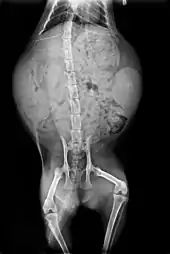

Anatomie des organes vitaux du chat.

Squelette et muscles

L'anatomie du chat est semblable à celle des autres espèces de félidés. Il possède un corps fort et flexible, des réflexes rapides, des dents pointues et des griffes rétractables adaptées à la mise à mort de petites proies.

Le squelette est composé de 250 os. Les vertèbres du cou sont courtes, et la colonne vertébrale est très souple.

La clavicule des chats, de petite taille comme pour tous les félins, est reliée au sternum par un unique ligament : cela lui confère une grande souplesse, les épaules pouvant bouger indépendamment l’une de l’autre. Comme tous les carnivores, la dernière prémolaire supérieure et la première molaire inférieure forment les carnassières qui permettent au chat de déchirer sa nourriture, grâce à des muscles puissants fixés aux parois latérales de son crâne, et de l’avaler sans la mâcher. L’os hyoïde est entièrement ossifié, ce qui permet au chat de ronronner mais pas de rugir[14].

Les pattes sont pourvues de griffes rétractiles. Le chat possède cinq doigts aux pattes antérieures, dont seulement quatre touchent le sol, le pouce restant à l’écart, ainsi que quatre doigts aux pattes postérieures[14]. Des cas de polydactylie existent et certains standards de races de chats l’admettent dans les concours[A 3]. Les coussinets ou pelotes, sont constitués d’une membrane élastique qui confère une marche silencieuse[15].

Vue externe et squelette du chat.